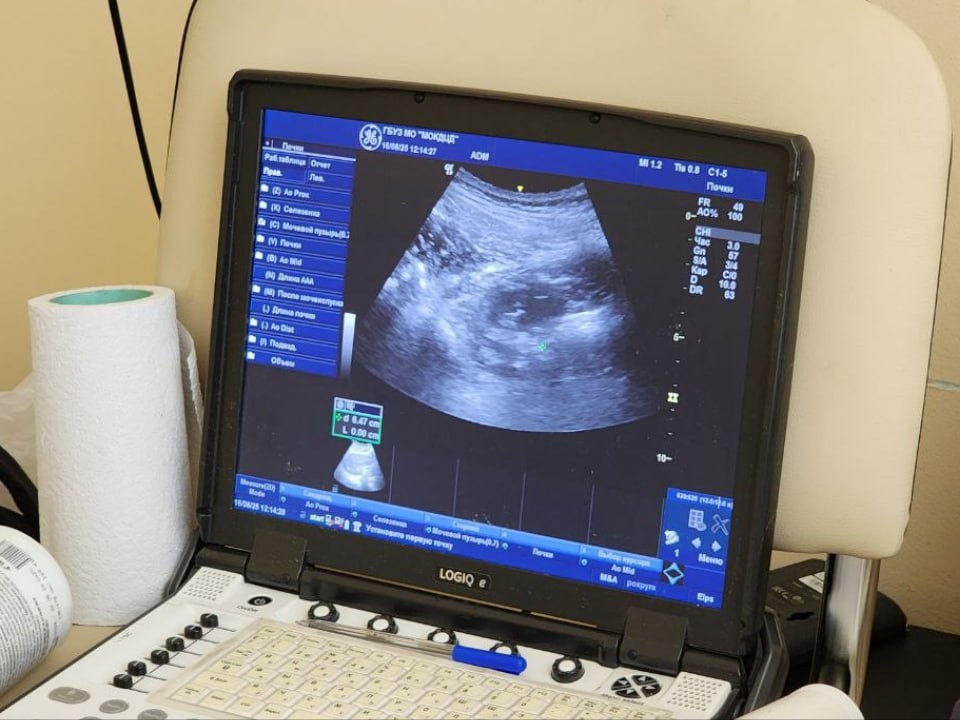

В ходе тестов проверялись ключевые параметры: компактность аппаратов, скорость их развертывания, простота подключения и качество диагностики. По данным Мининвеста, оборудование продемонстрировало высокие результаты по всем показателям.